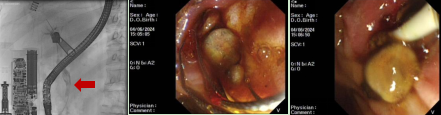

病例4

患者,男,74岁,主因“皮肤黄染5天”就诊我科,腹部CT提示肝外胆管及胆囊壁增厚伴强化,性质待定。既往高血压、冠心病病史,心脏搭桥术后、COPD病史。行内镜下逆行胰胆管造影发现胆总管上段有巨大结石,胆道梗阻,给予内镜下球囊扩张及胆总管取石治疗。

病例5

老年男性患者,主因“上腹部疼痛1天伴恶心呕吐”入院,既往糖尿病病史。腹部CT提示胆囊结石,胆总管内高密度灶,考虑胆总管结石,行内镜下逆行胰胆管造影术并及胆总管取石治疗。